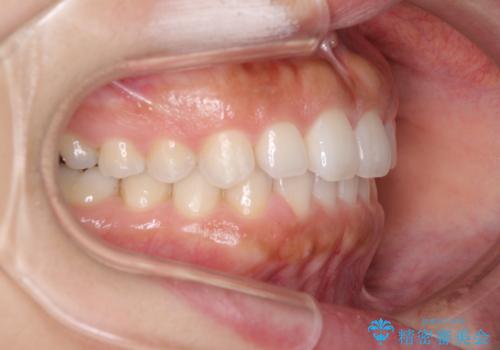

隙間の空いた前歯を閉じたい インビザライン矯正

- 前歯の隙間を気にして来院された患者様です。

隙間、捻転ともに軽微でありましたが、下顎前歯の突き上げにより隙間ができていたため、インビザラインを用いて咬み合わせを改善しながら前歯の歯列を整えていくこととしました。

当初は1年程度で終えられると思いましたが、治療途中から装着時間が短くなったり、来院間隔が長期になったりとし、結果として4年半以上の治療期間となりました。

治療途中に上顎前歯は失活してしまいましたが、変色が顕著ではないため、経過を見ていくこととなりました。